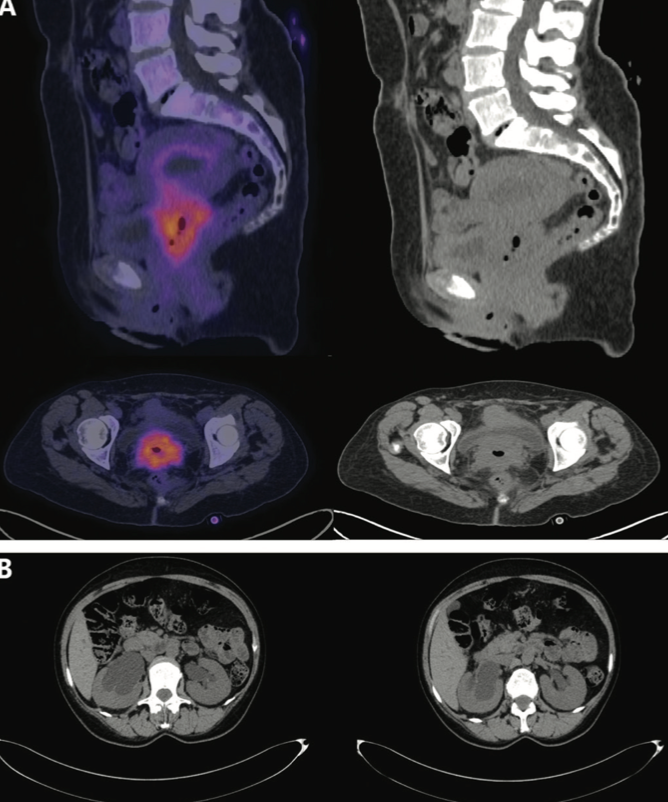

Basal PET-CT scan revealed an irregular, heterogeneous cervix. The lesion measured 48 x 59 mm and extended to the vagina, with a maximum standard unit value (SUVmax) of 12.2 and metabolic tumor volume (MTV) of 36.8 cm3. The scan also revealed lymphadenopathy of the left external iliac chain with the following dimensions: 13 mm, SUVmax of 9.4, and MTV of 1.58 cm3; left common iliac adenopathy of 10 mm, SUVmax of 4.2, and MTV of 2.49 cm3; and bilateral hydronephrosis (Figure 1).

FIGURE 1. Baseline PET-CT Scan (A) Local metabolic

activity in the cervix. The lesion measured 48 x 59 mm, extending to the vagina with SUVmax of 12.2 and MTV of 36.8 cm3. Lymphadenopathy of the left external iliac chain measured 13 mm with SUVmax of 9.4 and MTV of 1.58 cm3. Left common iliac adenopathy measured 10 mm with SUVmax of 4.2 and MTV of 2.49 cm3. (B) The presence of bilateral renal ectasia is evidenced. MTV, metabolic tumor volume; SUVmax, maximum standard unit value.